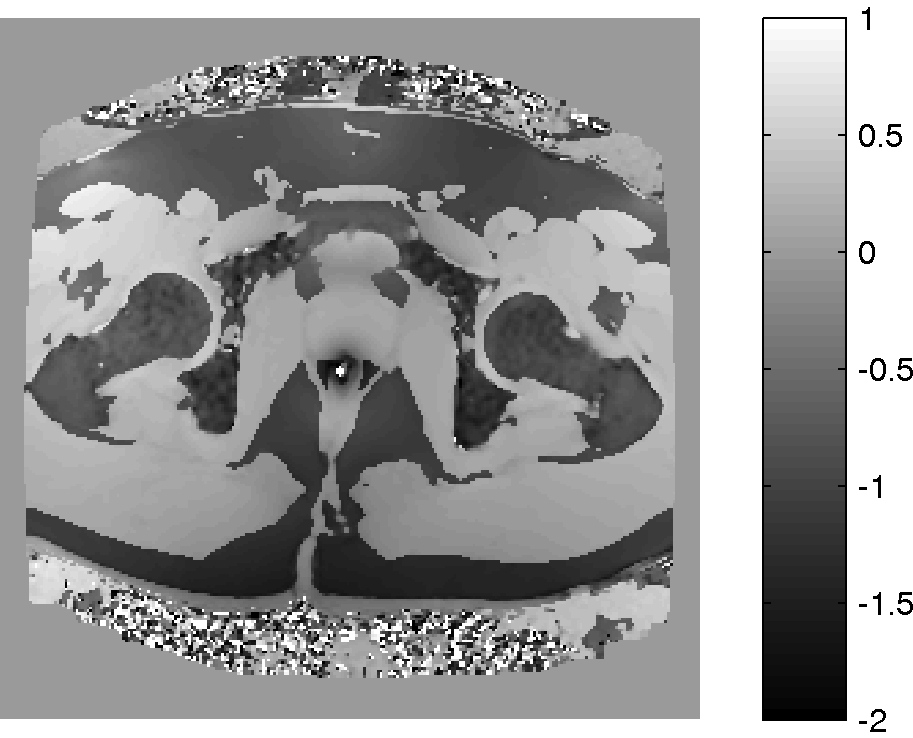

Refer to caption

(a) Magnitude image

(b) PPM map, Phi

(c) Corrected PPM map, 𝚽𝐡subscript𝚽𝐡\bf\Phi_{h}

(d) 𝚽𝐛subscript𝚽𝐛\bf\Phi_{b} field map

Figure 6: Background suppression of a ppm map with water and fat signal. (a): Magnitude of the first echo of a multi echo sequence. (b): PRF map estimation using ARMA technique.(c): Background suppressed PRF map. (d): Estimated background field map in ppm. The fat and water peak is aliased with 4.324.324.32 ppm due to the chosen echo spacing. the fat-water boundary. The labels 1 and 2 are water and fat ROIs that are used to determine the CNR gain of the method.

An MFGRE sequence was used to collect using a 3T scanner (SIGNA; GE Healthcare Technologies, Waukesha, WI) 16 echoes with echo spacing of 1.816ms1.816𝑚𝑠1.816ms, TR=75ms𝑇𝑅75𝑚𝑠TR=75ms, Matrix 128×128128128128\times 128 and Pixel Bandwidth of 651.016Hz651.016𝐻𝑧651.016Hz. Figure 6 (a) illustrates the magnitude of the first echo of a slice through the pelvis. The multi echo data is processed pixel wise by the ARMA technique. The resulting PRF in ppm at each pixel is illustrated in Panel (b). The dark areas in panel (b) are subcutaneous lipid. Inhomogeneities of the PRF can be seen near the air inclusion in the middle and throughout the image, in particular in the lipid regions. The result of the background suppression technique is shown in Panel (c), which illustrates, that most of the background inhomogeneities have been removed. Note the fat-water ppm difference is about 1.16ppm1.16𝑝𝑝𝑚1.16ppm and not the expected shift of about 33.5ppm33.5𝑝𝑝𝑚3-3.5ppm. This is a consequence of aliasing introduced by the finite sampling in echo direction. If the aliasing is taken into account by adding the bandwidth of 4.3212ppm4.3212𝑝𝑝𝑚4.3212ppm, then the fat-water shift is 3ppm3𝑝𝑝𝑚3ppm as expected. The pixel wise difference of the images in Panels (b) and (c) is shown in Panel (d). Note that the estimated background field 𝚽𝐛subscript𝚽𝐛{\bf\Phi_{b}} is smooth in areas of transitions of fat and water. The map is not necessarily smooth in areas of low signal, however a correct estimation of the background in low signal areas is not a well-posed problem.